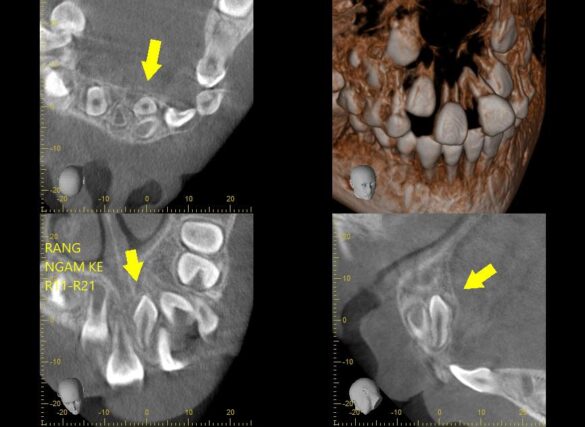

#khớpcắnhở #openbite Dr. Thy Nga Nguyen